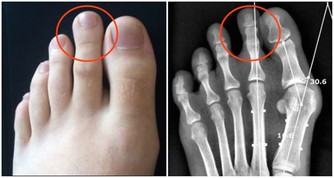

為什麼過年時多?兩個原因,一個是高凝體質血稠,就是脂肪高。

大家記住,

血稠的人叫高凝體質。高凝體質的人加上高凝食物,

所以過年時心肌梗死的人特別多,年齡不限。

心肌梗死雖然無法治,但完全可以預防。有的大夫告訴你吃阿司匹林,